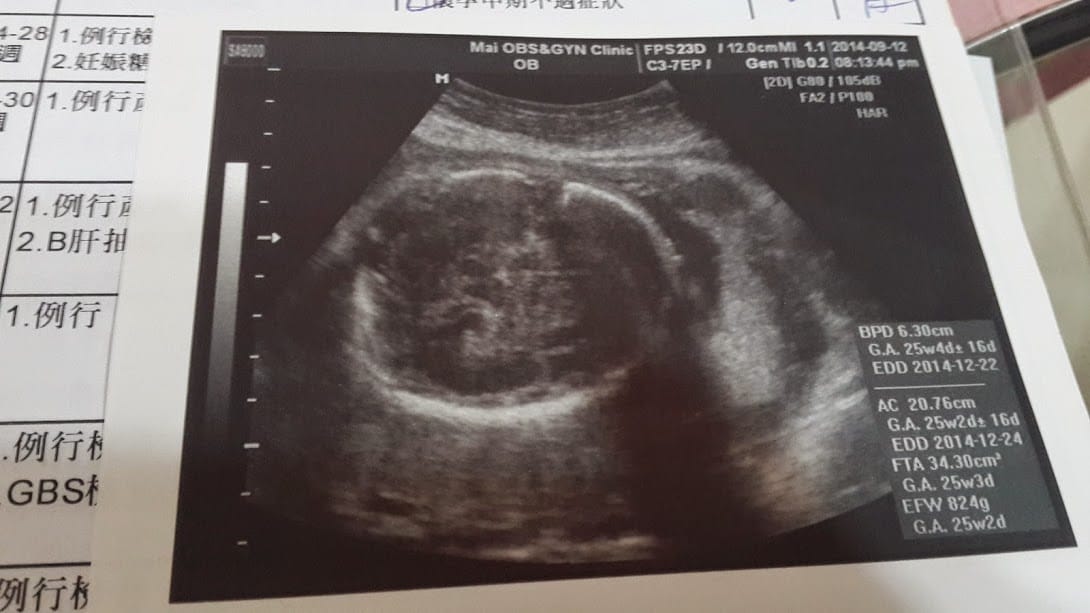

小三體重預估:2690g

不過產檢時徐醫生說寶寶的頭圍正常,身體卻大了兩周,怕臨盆時身體太大會難生,要少吃甜的東西